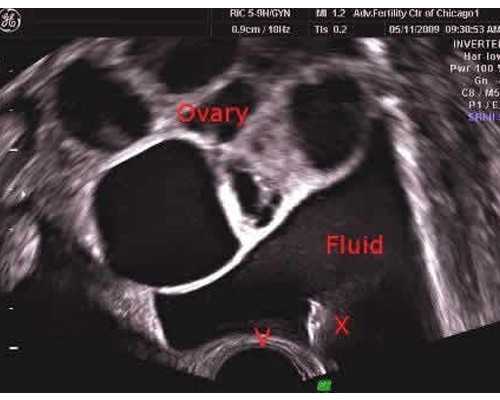

唐氏筛查便是为了防备因为染色体反常所导致的疾病,翻开凤凰新闻,检查更多高清图片,但因为它的原理,所以唐筛准确率并不高,约在70%—80%左右,穿刺术的具体方法如下:凭借超声波的指示,运用一根又细又长的穿刺针顺次经过孕妇的肚皮、子宫壁,最终抵达羊水中,抽出适量的羊水,之后做相关的剖析以及标本等,据此判别胎儿在腹中是否发育正常。